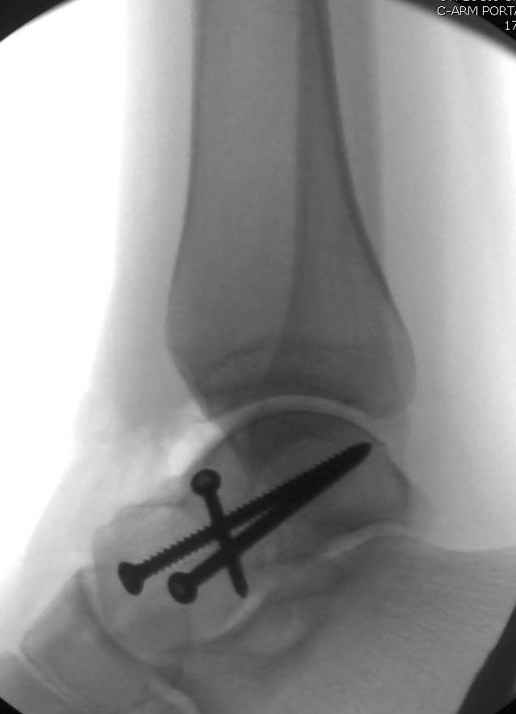

Вдогонку по поводу перелома таранной кости, больная 81, не страдает диабетом, перелом закрытый, в первый же день поступления ограничились временным наружным фиксатором (как на снимке).

Из-за отека на стопе тактика лечения у всех была

одинаковая: временная наружная фиксация до спадения отека, при изолированных переломах они выписывались домой и через дней 7 госпитализировались на оперативное лечение.

Примеры на снимке...